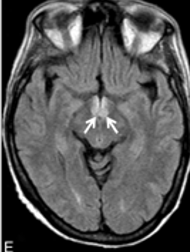

c-shaped fiber tract from hippocampus

myelinated afferent & efferent fibers

splits from hippocampus

continues to anterior commissure

fornix

fornix function

episodic memory

fornix clinical issues:

may relate to Alzheimer’s disease

hypothesized to degenerate and amount of degeneration may relate to severity of cognitive impairment